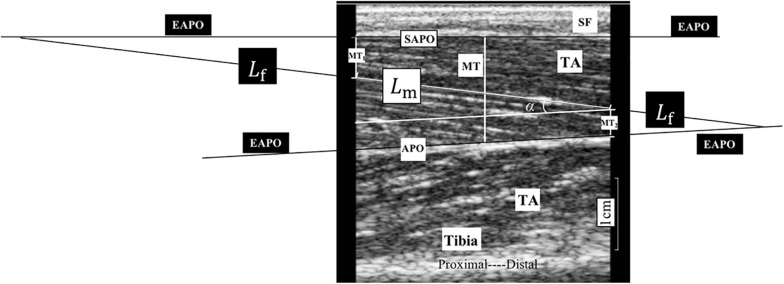

Ultrasonography was performed using a B-mode ultrasonography scanner (DP6600, Mindray Inc., China) with a 7.5-MHz, 38-mm probe (imaging resolution, 0.3 mm; frame rate, 25/s). During the examination, the ultrasound probe was placed perpendicularly to the muscle fibers of the TA muscle between the two inner voltage electrodes (Figure 1). Coupling gel was applied before the examination to enhance the ultrasound conduction between the probe and the skin surface. Three ultrasound measurements were recorded at each ankle joint angle, and the average was calculated for statistical analysis. The images recorded at each of the measuring joint angles were saved for the calculation of the muscle morphology parameters. A typical ultrasound image of the TA muscle is shown in Figure 2. The PA, MT, and FL were calculated from the ultrasound image. The PA was directly measured from the image. The MT was calculated as the average of the values obtained between the two edges of the TA muscle in the image. Muscle FL was estimated using a trigonometry method, which assumed a linear continuation of the muscle fascicle (Reeves and Narici, 2003; Li et al., 2007). Equation 1 was used to derive the muscle FL:

FIGURE 2.

A typical ultrasonography image of non-paretic tibialis anterior (TA) from a participant during assessment. MT1 and MT2 are the distance of the visible fiber distal end point to the superficial aponeurosis and the distance of the visible fiber proximal end to the aponeurosis, respectively; and α is the pennation angle (PA). We considered the middle thickness of captured image as the muscle thickness (MT) of the TA, so we measured, respectively, the thickness of both left and right edges of the TA in the image and take the average value of these two measurements as MT for statistical analysis. APO, aponeurosis; EAPO, extension of the visible aponeurosis; SAPO, superficial aponeurosis; Lf, entire estimated muscle fascicle length; Lm, visible part of the muscle fiber in the image; MT, muscle thickness; SF, subcutaneous fat; TA, tibialis anterior.

where Lf is the entire estimated muscle FL; Lm is the visible part of the muscle fiber; MT1 and MT2 are the distances from the fiber distal endpoint to the superficial aponeurosis and from the fiber proximal endpoint to the aponeurosis, respectively; and α is the PA (Figure 2).